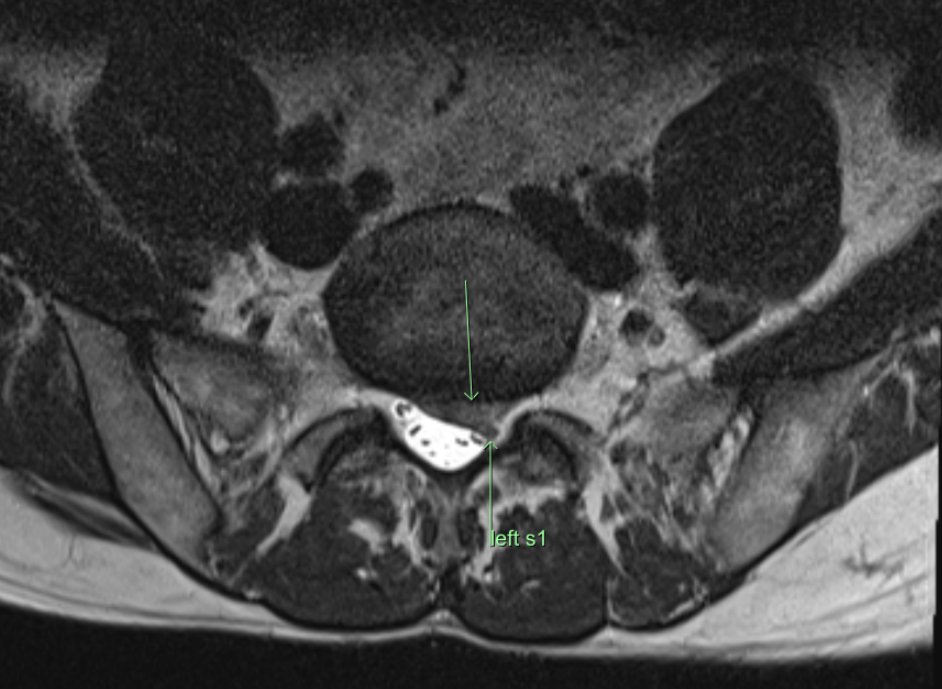

Consent✅ 1 year progressive severe (painless) L calf atrophy & weakness Medial bulk affected > lateral - see pic Affecting football performance Rolling over in bed onto R side - sudden 'spasms' in leg leg US - diffuse fatty atrophy of medial gastroc & soleus (vs R) EMG / NCS - severe L5 & S1 subacute chronic radiculopathy MRI - no herniated disc - but 5cm filum terminale lipoma (high signal on T1 seq, low on STIR). Also very low lying conus medullaris & tethered cord suggestive of spinal dysraphism (spina bifida occulta) Neurosurgical referral